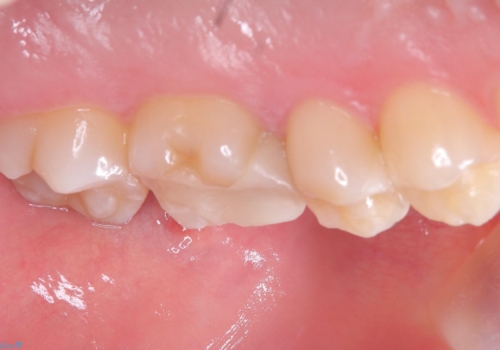

適合性、審美性、材料安定性からセラミックインレーでのやり替えとなりました。う蝕を除去いていくと、残存歯質が薄く破折リスクの高い部位が出てきたため患者さんにも説明し、アンレー窩洞としました。

セラミックアンレー接着時は、ラバーダム防湿を行っています。